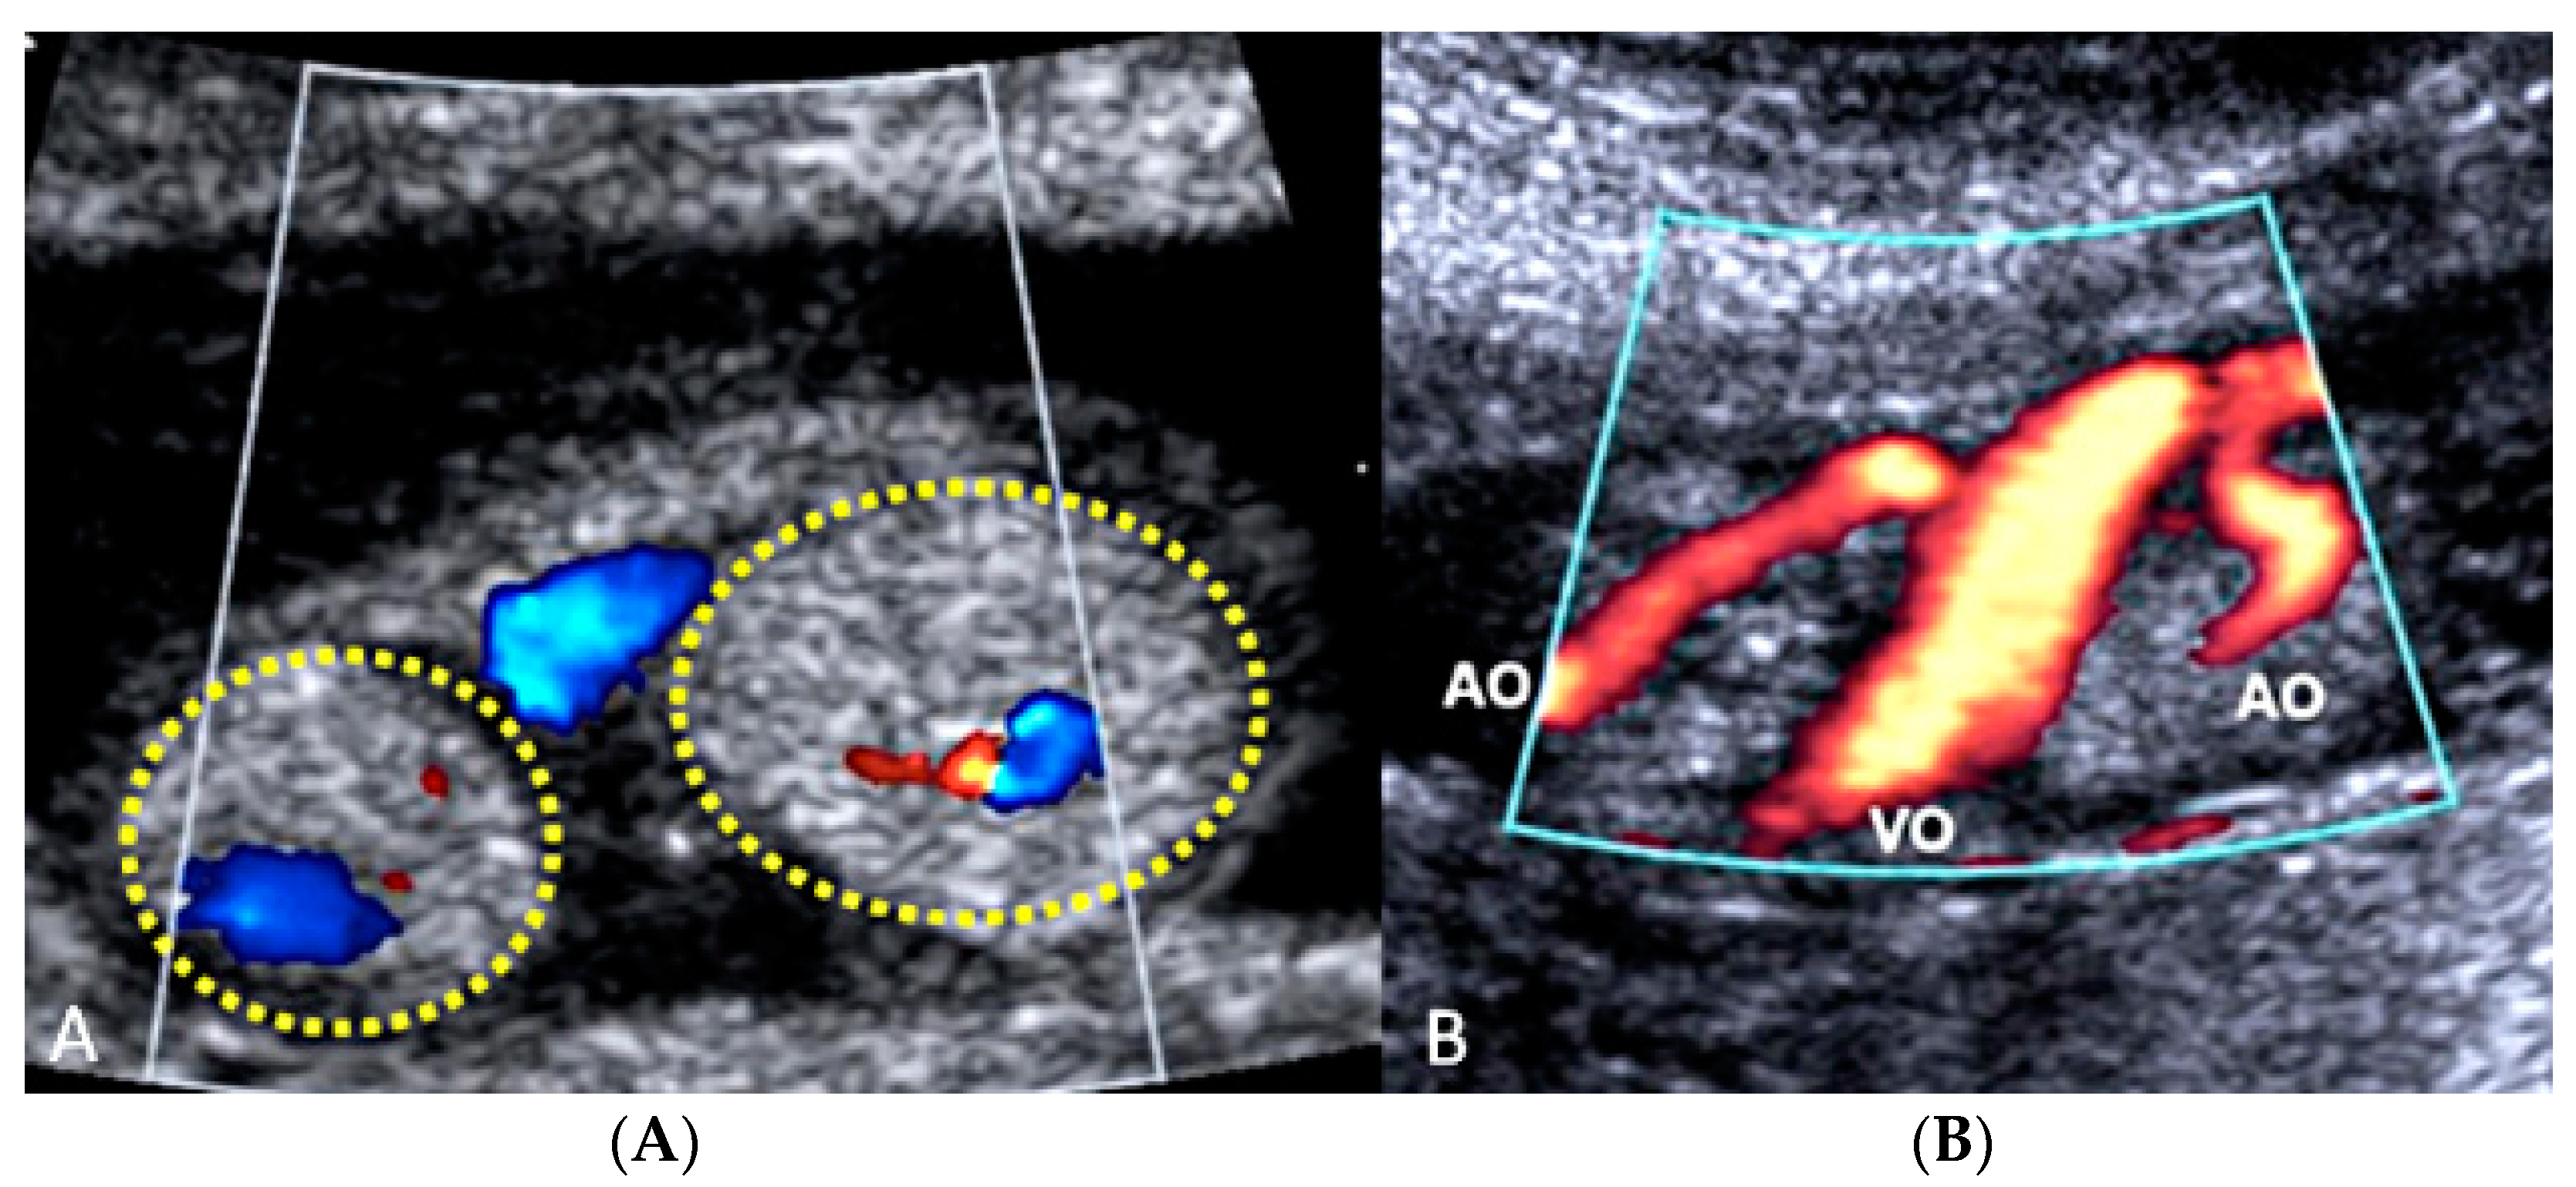

3.2.2. Vasa Praevia

3.2.3. Velamentous Umbilical Cord Insertion